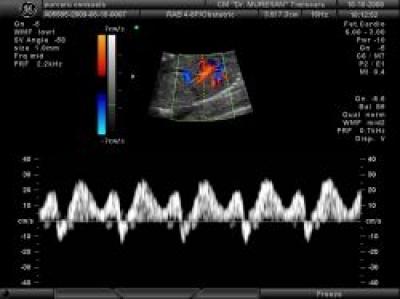

Centrul de Medicina Fetala - Dr. Muresan

Importance of the 11-13 weeks scan

The 11-13 weeks scan provides the most effective method of early screening for trisomy 21 and other major chromosomal abnormalities. Screening by nu... Citeste mai departe